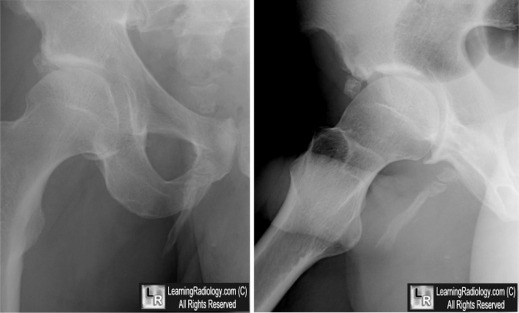

Pelvic Digit. (Above). Frontal and lateral radiographs of the hip demonstrate a well-corticated bony protuberance arising from the region of the right pubic bone with a suggestion of segmentation (yellow and white arrows). (Below) A coronal reformatted CT image of the pelvis confirms the presence of the pelvic digit with pseudo-articulations (white circle).

For these same photos without the arrows, click here and here